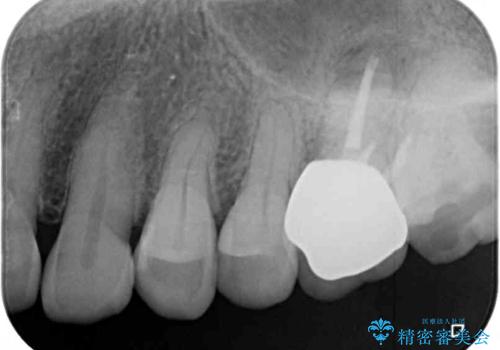

- 奥歯に装着したクラウンの周りに汚れが溜まりやすいとのことで来院された患者様です。

既に装着されているクラウンの質は決して悪いものではありませんでしたが、患者様自身が非常に気にしていたため、作り替えの治療を行うこととしました。

根管治療が必要と思えるような所見も認められませんでしたが、一緒に行いたいとの希望があったため、根管治療を行った上で補綴治療を行うこととしました。

クラウン装着後は、特にものが挟まる感覚もなく、快適に過ごすことができるようになりました。